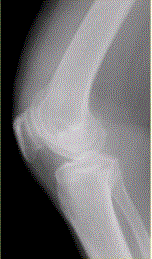

问题 患者女,54岁,右膝关节痛。实验室检查:类风湿因子阳性,除外膝关节类风湿性关节炎。X线检查结果如下图。 观察X线平片后,最可能的诊断是

选项 A.膝关节退行性骨关节炎 B.膝关节类风湿性关节炎 C.膝关节色素沉着绒毛结节性滑膜炎 D.膝关节滑膜型结核 E.血清阴性脊椎关节炎膝关节侵犯

答案 A